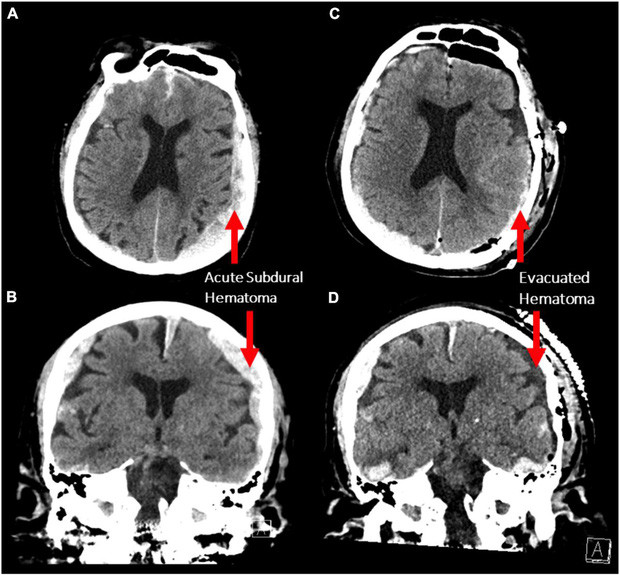

Các nhà khoa học thần kinh đã vô tình ghi lại được quá trình hoạt động của bộ não sắp chết trong khi họ đang sử dụng phương pháp ghi điện não đồ (EEG) để điều trị cơn động kinh ở một người đàn ông 87 tuổi.

Bệnh nhân bị nhồi máu cơ tim đột ngột và qua đời sau đó không lâu. Đây là lần đầu tiên trong lịch sử các nhà khoa học ghi lại được hoạt động của bộ não người sắp chết.